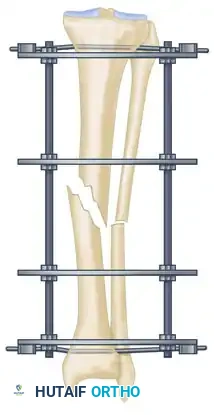

The management of complex, comminuted, or open tibial shaft fractures presents a formidable challenge to the orthopedic surgeon. The Ilizarov external fixation system, pioneered by Professor Gavriil Ilizarov, revolutionized the treatment of these injuries by introducing the concept of the tension-stress effect. Unlike rigid internal fixation, the Ilizarov circular frame utilizes tensioned fine wires to provide exceptional shear and torsional stability while permitting controlled axial micromotion. This unique biomechanical environment stimulates robust secondary bone healing (callus formation) without the need for extensive soft tissue stripping at the fracture site.

The efficacy of the Ilizarov frame relies on the precise geometric arrangement of rings and tensioned wires. Standard fine wires (1.5 mm to 1.8 mm) are tensioned to 110–130 kg, transforming them from flexible filaments into rigid beams capable of supporting physiological loads.

Step 4: Eliminating Residual Distraction

Following multi-planar correction, it is imperative to assess the fracture site for any residual longitudinal distraction. Distraction gaps inhibit secondary bone healing and lead to nonunion. Adjust the longitudinal threaded rods to compress the fracture site and eliminate any residual distraction.